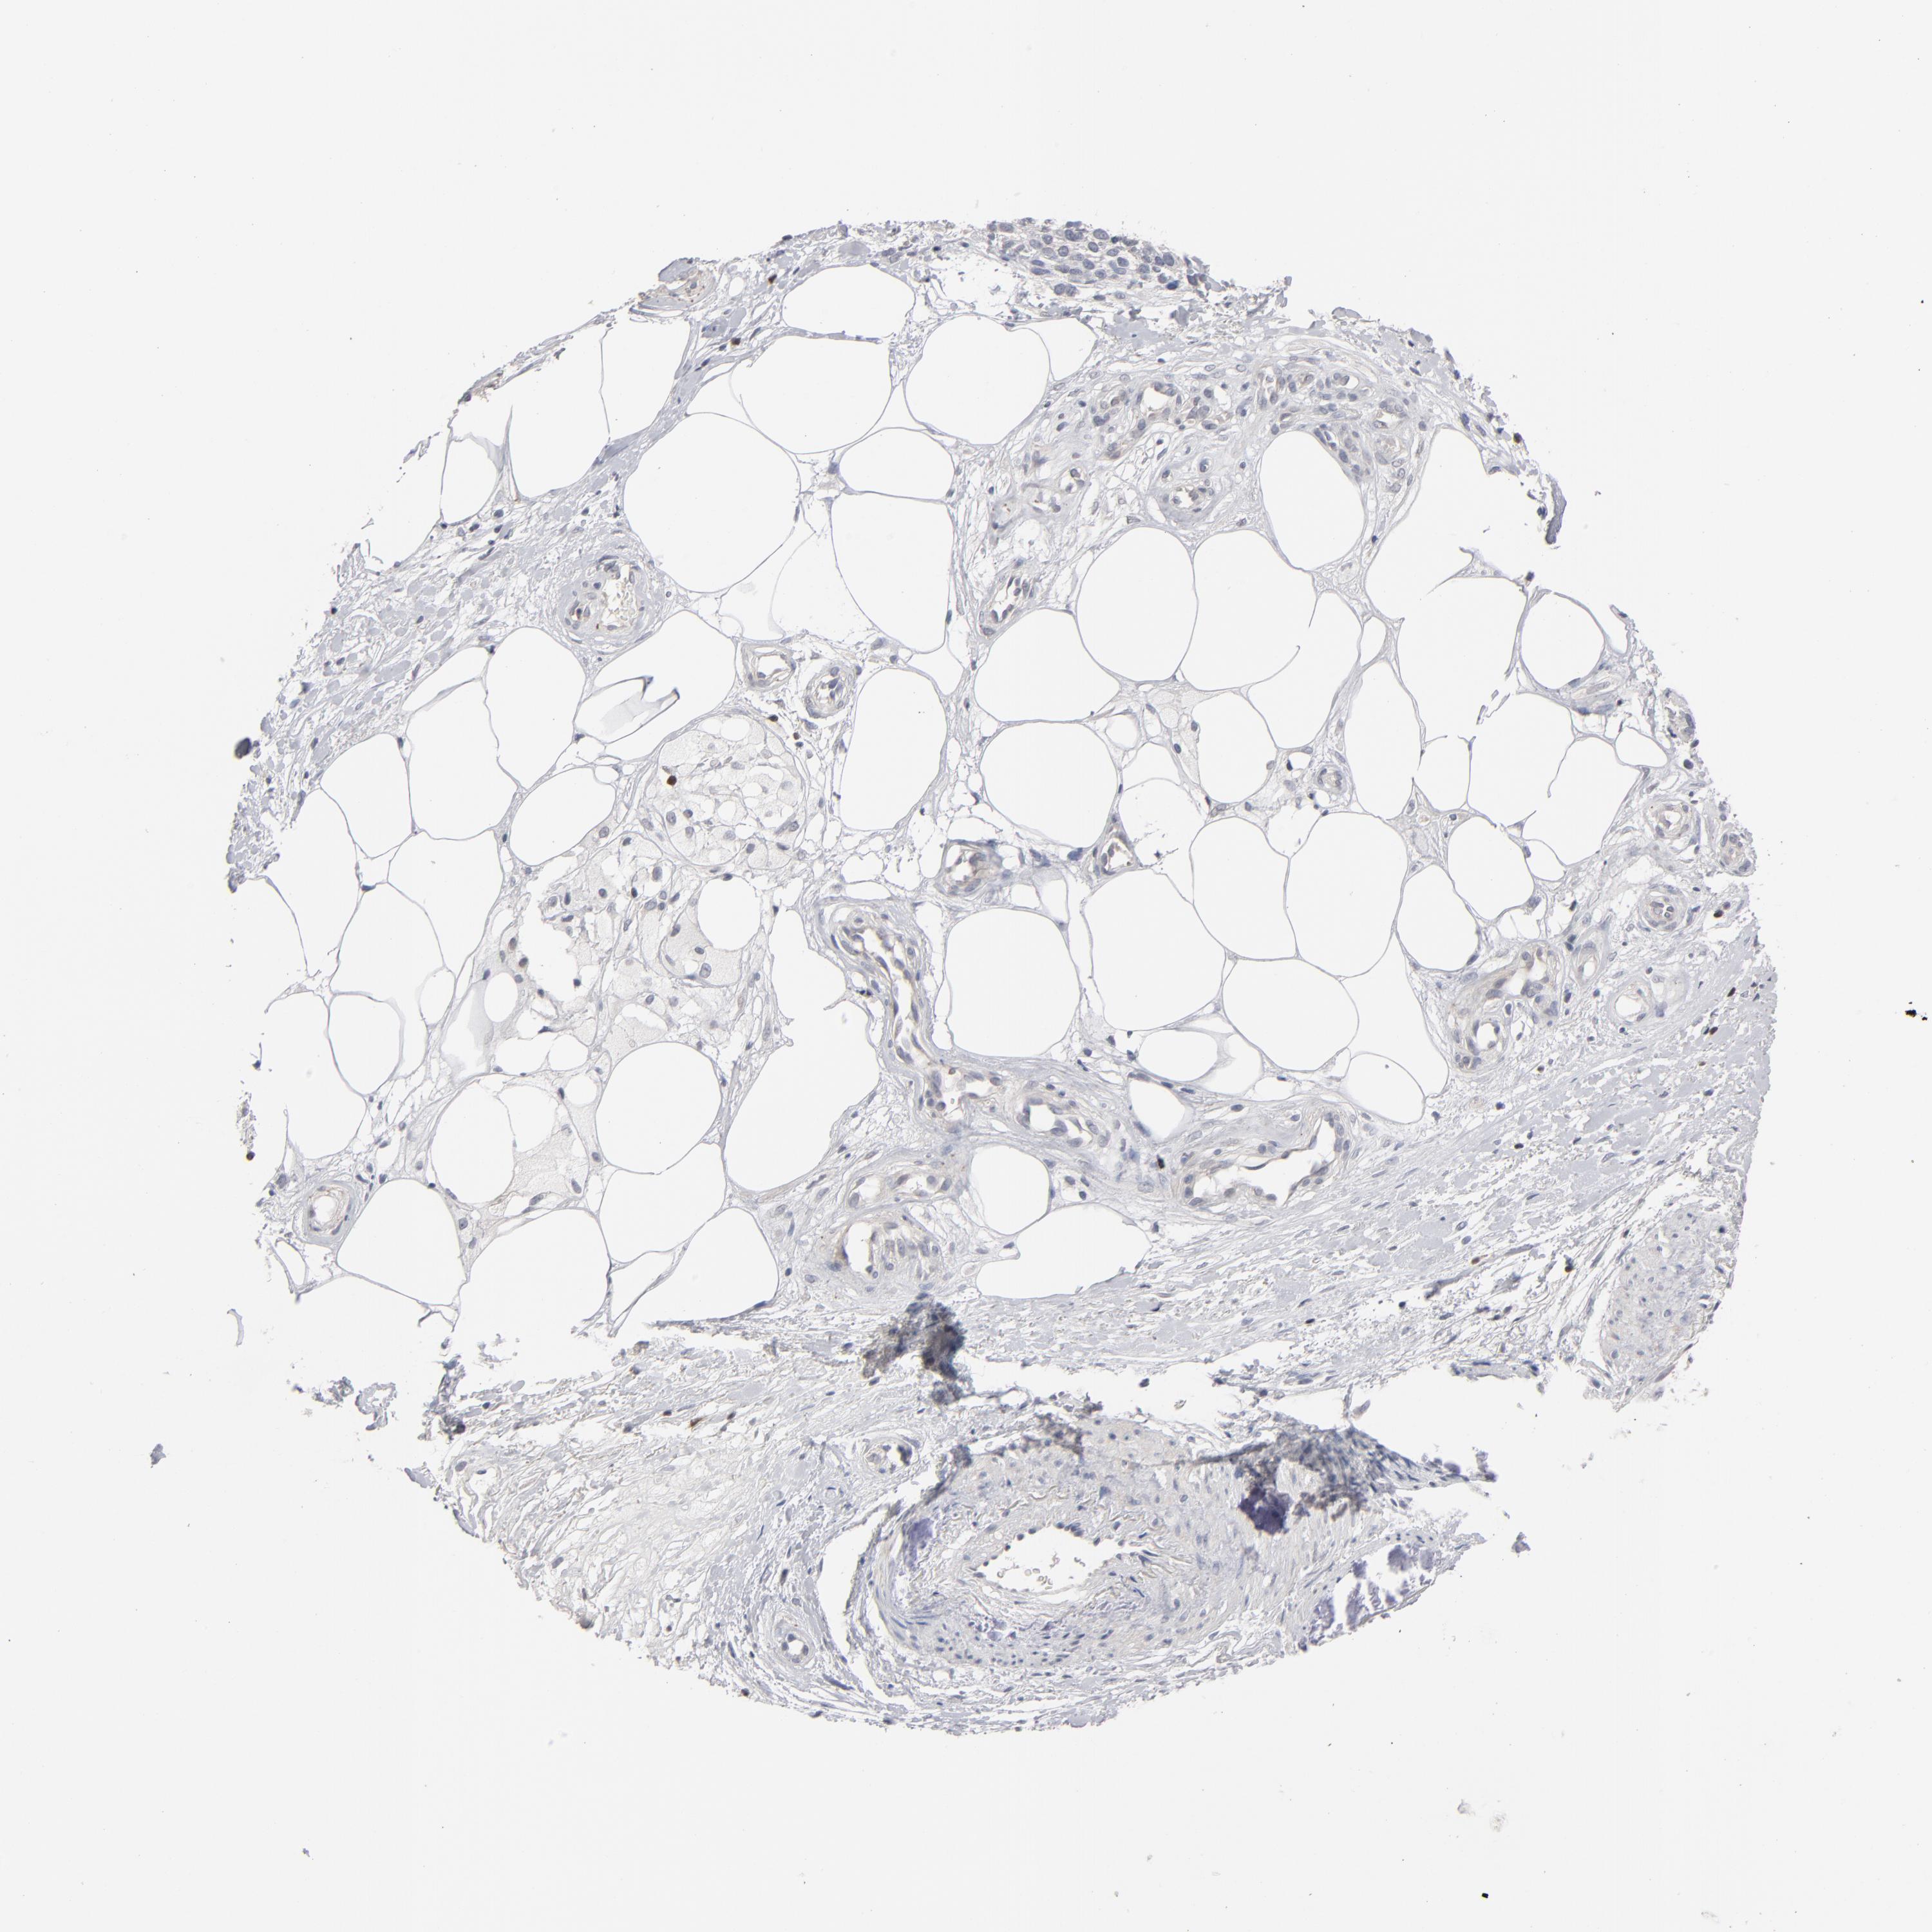

MELANOMA - Protein expressioni

A mouse-over function shows sample information and annotation data. Click on an image to view it in a full screen mode. Samples can be filtered based on level of antibody staining by selecting one or several of the following categories: high, medium, low and not detected. The assay and annotation is described here.

Note that samples used for immunohistochemistry by the Human Protein Atlas do not correspond to samples in the TCGA dataset.

Antibody stainingi

Antibody staining in the annotated cell types in the current human tissue is reported as not detected, low, medium, or high, based on conventional immunohistochemistry profiling in selected tissues. This score is based on the combination of the staining intensity and fraction of stained cells.

Each image is clickable and will lead to virtual microscopy that enables deeper exploration of all samples and also displays staining intensity scores, fraction scores and subcellular localization as well as patient and tissue information for each sample.

Antibody HPA001860

Antibody CAB013108

Malignant melanoma, NOS

Malignant melanoma, Metastatic site